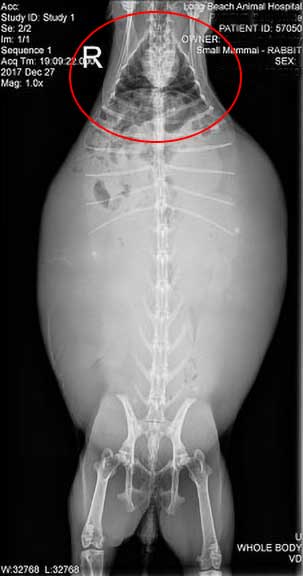

This rabbit radiograph shows a significantly distended abdomen. The distention is due to a uterus completely filled with fluid.

This is the same rabbit laying on its back. Even though rabbits normally have a large abdomen, this one is particularly large, making it hard for this rabbit to breathe. The thorax, containing the white colored heart and black colored lungs, is circled in red.